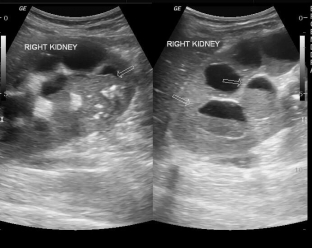

- ультразвукове дослідження: нирка збільшена у розмірах, має нерівні контури, спостерігаються ехонегативні утворення різного розміру з ехоструктурними включеннями, зумовлені гнійним вмістом;